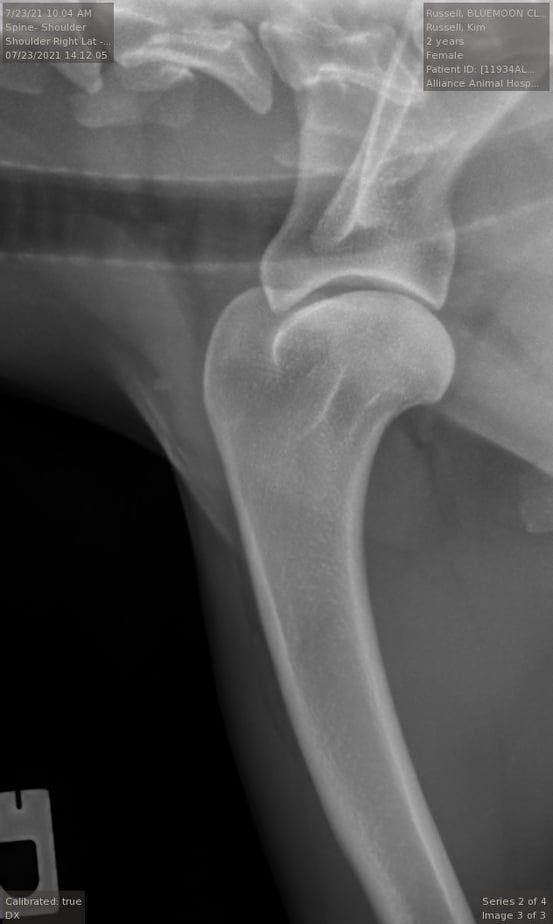

OFA Good, shoulders/elbows normal